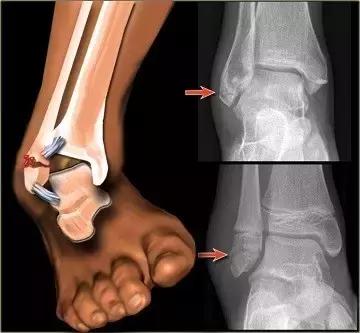

如果有,则存在骨折、骨裂、韧带附着端撕裂的可能性很大。当然,仅凭主观感觉难以100%确认,待伤情平稳后可到外科门诊行X光检查,以明确诊断。